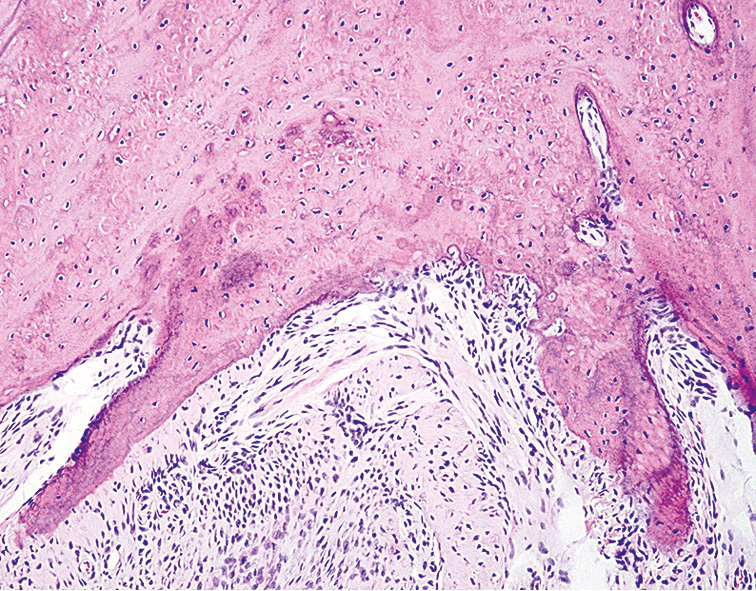

Гистологическое исследование позволило установить, что через 1 мес от начала эксперимента в слизистой оболочке пасти (СОП) животных выявляли морфологические изменения ткани с неравномерной атрофией, сглаживанием эпителиальных сосочков и гиперхромией клеток базального слоя. Под эпителием в клеточно-волокнистой строме определялись единичные кровеносные сосуды, а также пласты хрящевой ткани, в основном веществе которой видны единичные зрелые хондроциты (рис. 1).

Рис. 1. Слизистая оболочка пасти животного (опытная группа) через 1 мес от начала эксперимента. Окраска гематоксилином и эозином, ×120.

Fig. 1. The mucous membrane of the animal’s mouth (experimental group) after 1 month from the start of the experiment. Staining with hematoxylin and eosin, ×120.